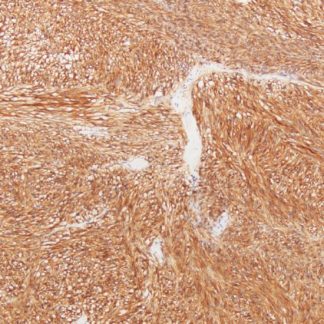

PLAP Antibody (Immunohistochemistry)

The PLAP (Placental Alkaline Phosphatase) Antibody is an important IHC marker.

It helps identify germ cell tumors and related neoplasms with high diagnostic value.

Moreover, PLAP positivity commonly appears in Seminoma,

Embryonal Carcinoma, and Placental Site Trophoblastic Tumors.

As a result, its membrane or cytoplasmic staining pattern becomes a strong indicator of germ cell origin.

- Clear brown membrane or cytoplasmic staining in positive cells